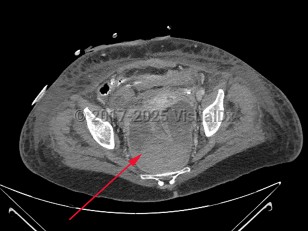

Imaging Studies image of Perirectal abscess - imageId=7915658. Click to open in gallery.  caption: '<span>Axial CT image of a  large perirectal abscess with hemorrhage in a patient recently  postoperative with rectal perforation.</span>'

Axial CT image of a large perirectal abscess with hemorrhage in a patient recently postoperative with rectal perforation.